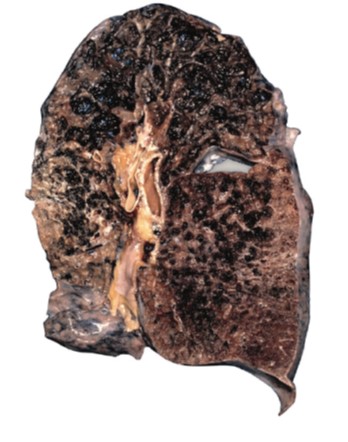

4. Smoking causes lung cancer

9. Smoking causes emphysema

damages your lungs”.